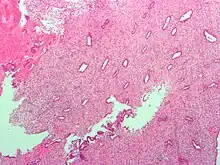

(A) proliferative endometrium (Left: HE × 400) and proliferative endometrial cells (Right: HE × 100)

(B) secretory endometrium (Left: HE × 10) and secretory endometrial cells (Right: HE × 10)

(C) atrophic endometrium (Left: HE × 10) and atrophic endometrial cells (Right: HE × 10)

(D) mixed endometrium (Left: HE × 10) and mixed endometrial cells (Right: HE × 10)

(E): endometrial atypical hyperplasia (Left: HE × 10) and endometrial atypical cells (Right: HE × 200)

(F) endometrial carcinoma (Left: HE × 400) and endometrial cancer cells (Right: HE × 400).